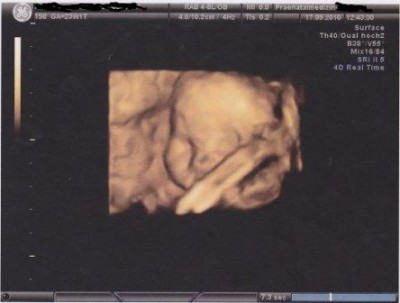

Anbei noch ein 3 D Bild von unserem Sohn.

Unser Sohnemann bei 23+1 am 17.09.2010